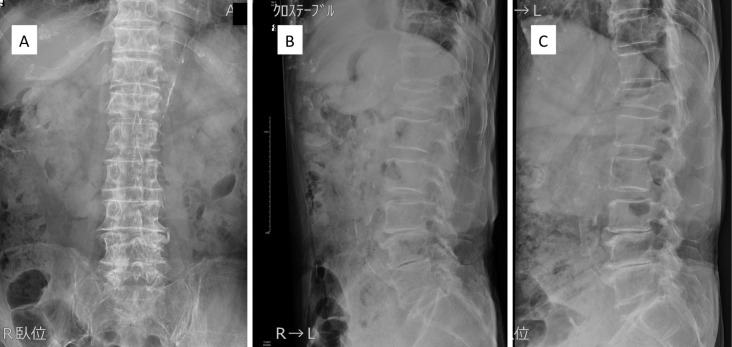

Methods: Surgical indications are a vertebral wedge angle difference of 10° or more, vertebral pedicle fractures, posterior wall fractures, and diffuse low-signal changes exceeding 50% on T1-weighted magnetic resonance imaging. The procedure is reserved for highly unstable cases following a comprehensive health assessment. The surgical technique involves prone positioning, fluoroscopy-guided percutaneous vertebral augmentation, and the use of downward PES in the cranial vertebral body and upward PES for the caudal vertebral body by percutaneous technique. The fixation range is one above and one below.

Abstract Image